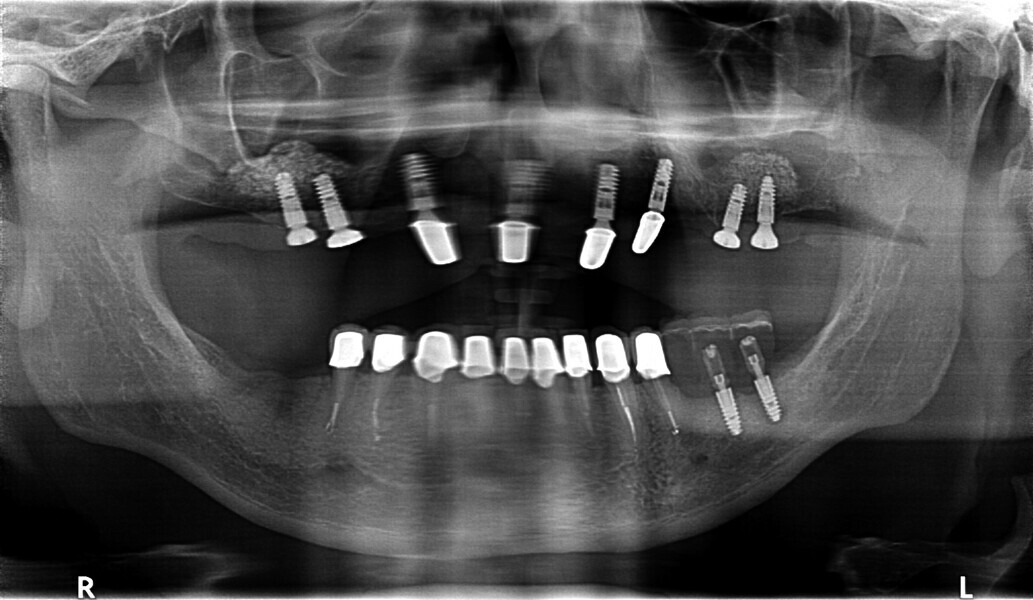

Fig. 30: OPG after placing implants.